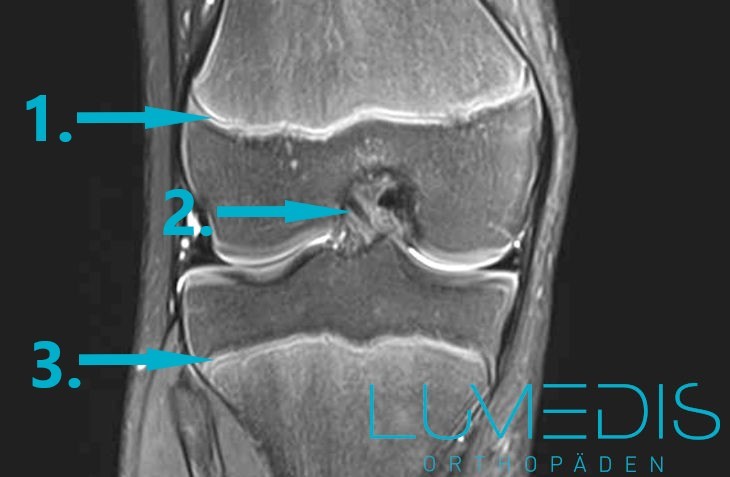

MRT eines Kniegelenks im Wachstum beim Kind

Die Kernspintomographie (MRT) ist in der Regel keine Routineuntersuchung zur Diagnose von Wachstumsschmerzen. Sie kann in Betracht gezogen werden, da die Strahlenbelastung eines CT- oder Röntgenbildes für ein Kind häufig als zu hoch eingeschätzt wird. Sie stellt die Weichteile besonders gut dar, so dass Gelenkveränderungen wie Bänder, Knorpel oder Verstauchungen gut dargestellt werden können. Bei dringendem Verdacht auf einen Tumor kann sie zur genauen Tumordifferenzierung eingesetzt werden.